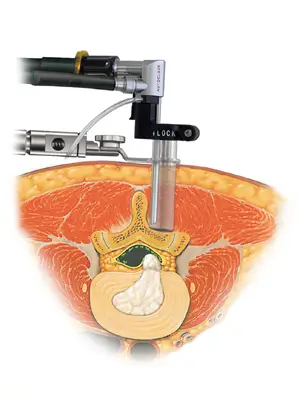

内視鏡システム | エム・シー・メディカル株式会社。脊椎内視鏡手術|平井整形外科クリニック|横浜市港北区綱島の。脊椎内視鏡センター|脊椎脊髄末梢神経外科|新百合ヶ丘総合病院。内視鏡手術の基礎から応用までを網羅した実用書。神経内視鏡手術 | 藤田医科大学 医学部 脳神経外科学講座。- タイトル: スタンダード 内視鏡手術- 出版社: MEDICAL VIEW1度も読んでいない新品ですが素人の自宅保管になりますので、完璧な新品を求めている方は落札をご遠慮下さい。裁断済み‼️スキャナーが必要です‼️皮膚科の処方ノート 2023。他にも多数出品しておりますので是非宜しくお願い致します。4冊セット 標準理学療法学。自己紹介文を必ず読んでから購入お願い致します。【裁断済み】 内科学 第12版 全6巻セット 朝倉書店。